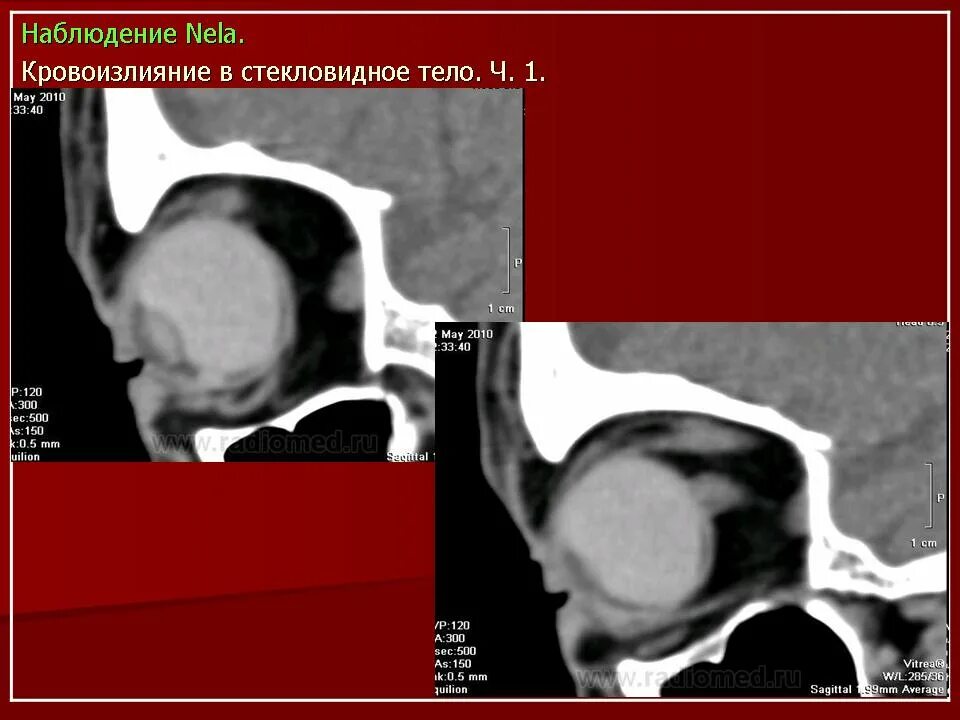

Данные кт